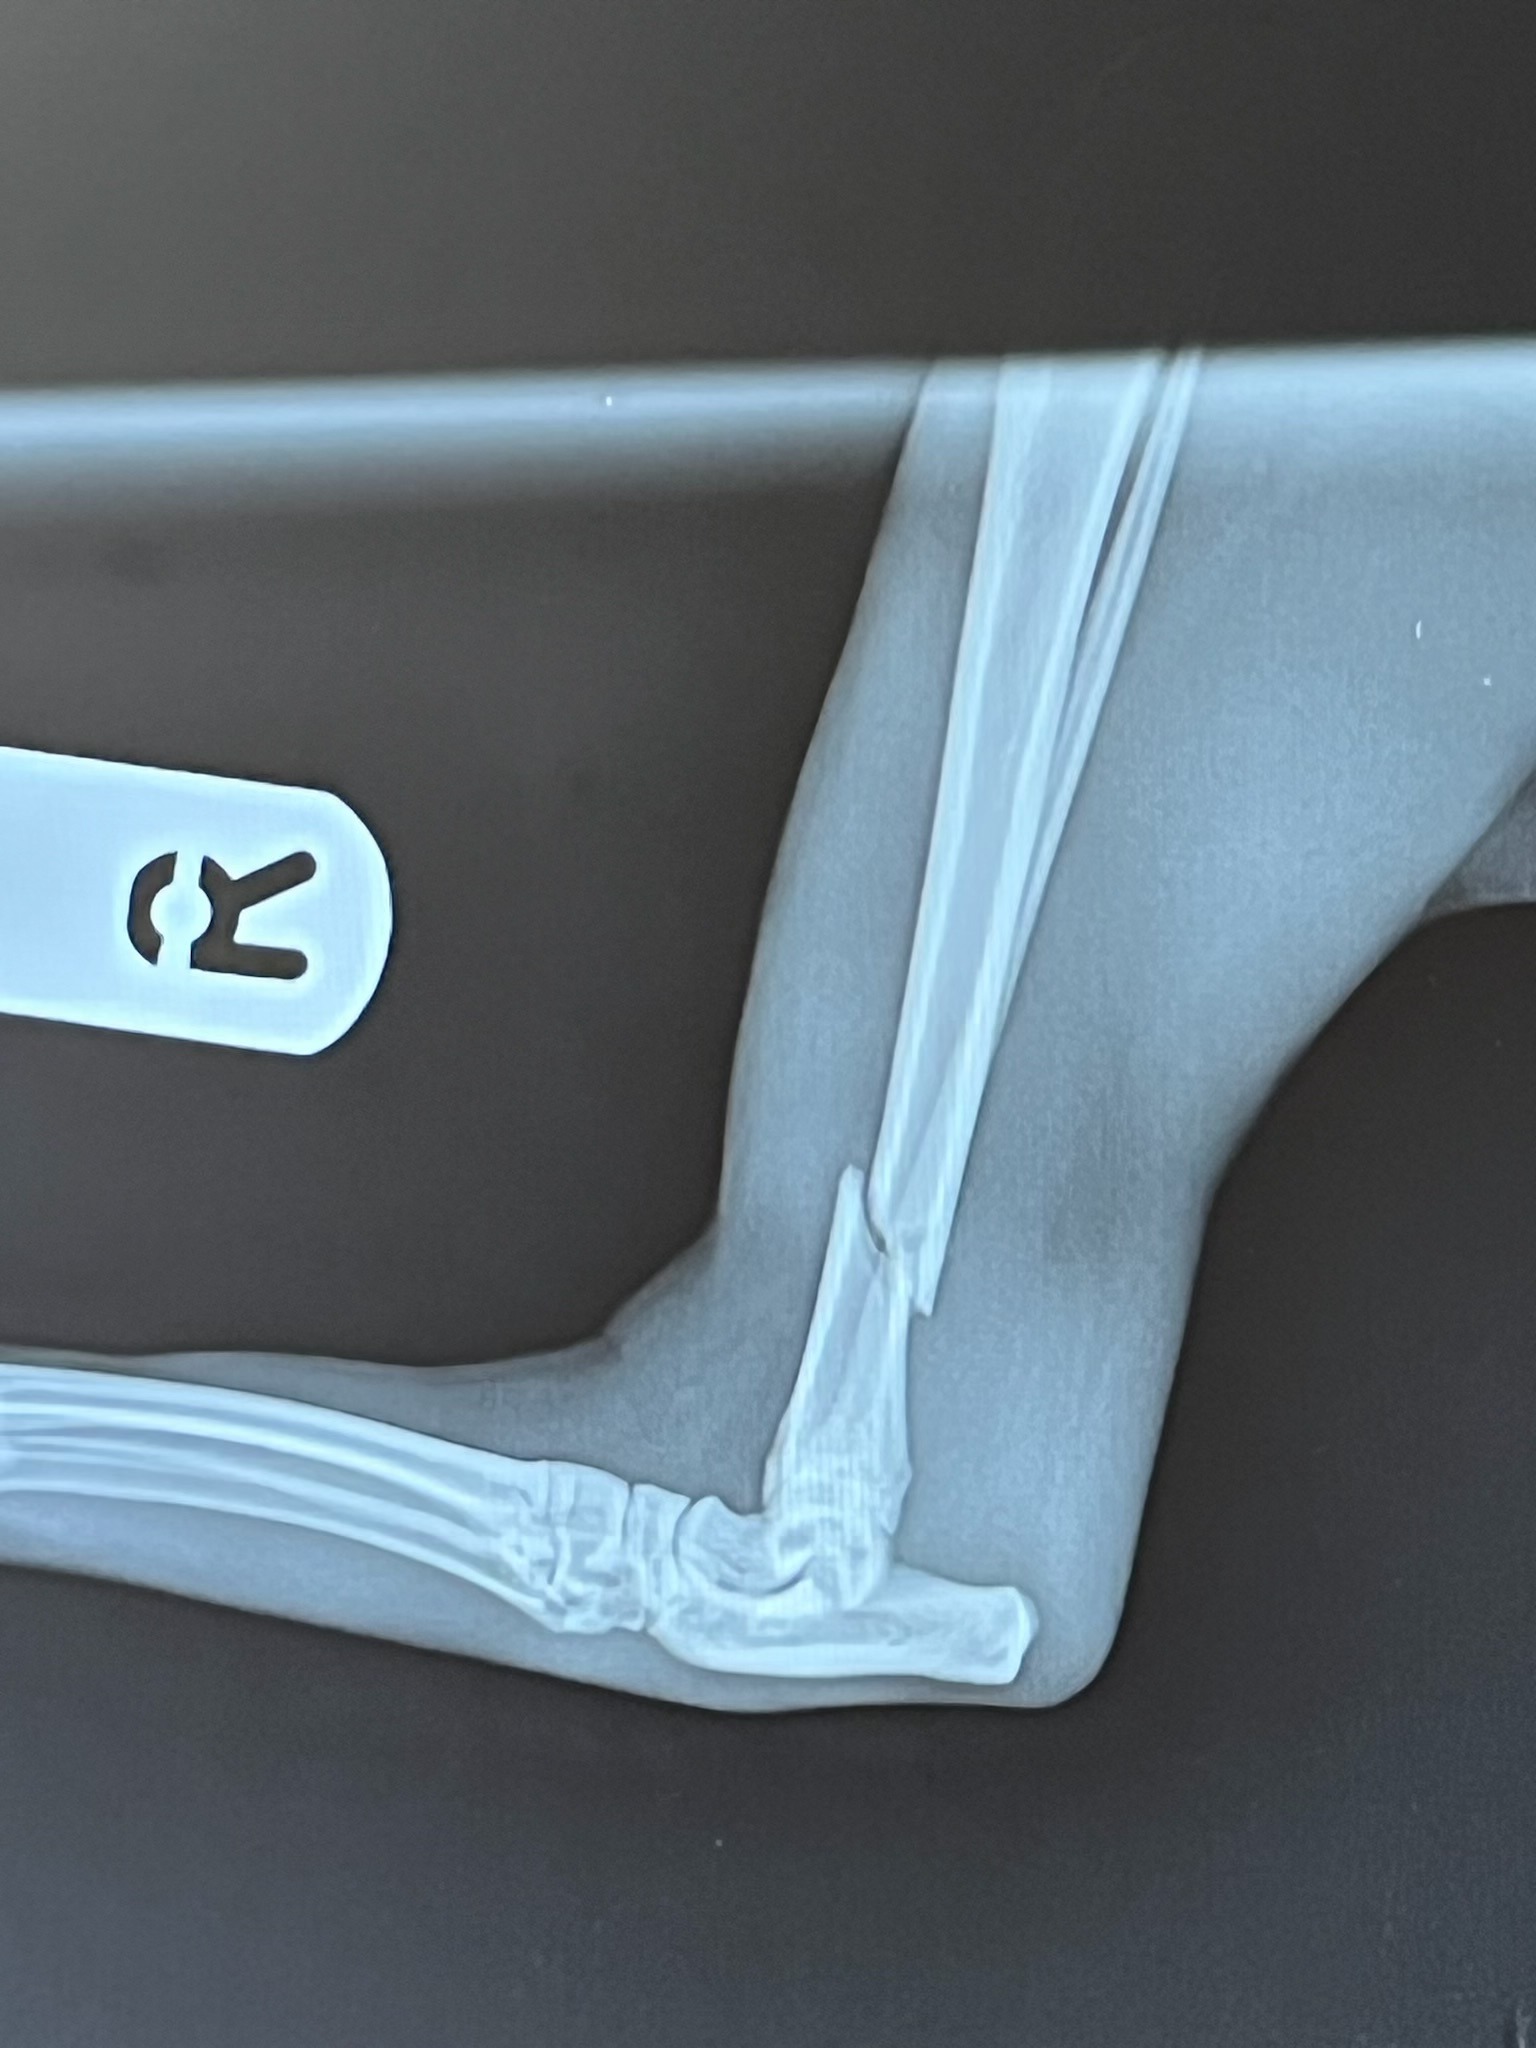

I am very upset and in pain for her as Indie has broken her hind right leg.

Having spent £300 already to have her leg x-rayed and casted, I am asking if anyone would like to help raise a bit of money so that I have enough, comfortably, going forward with the next set of vet bills I will need to pay.